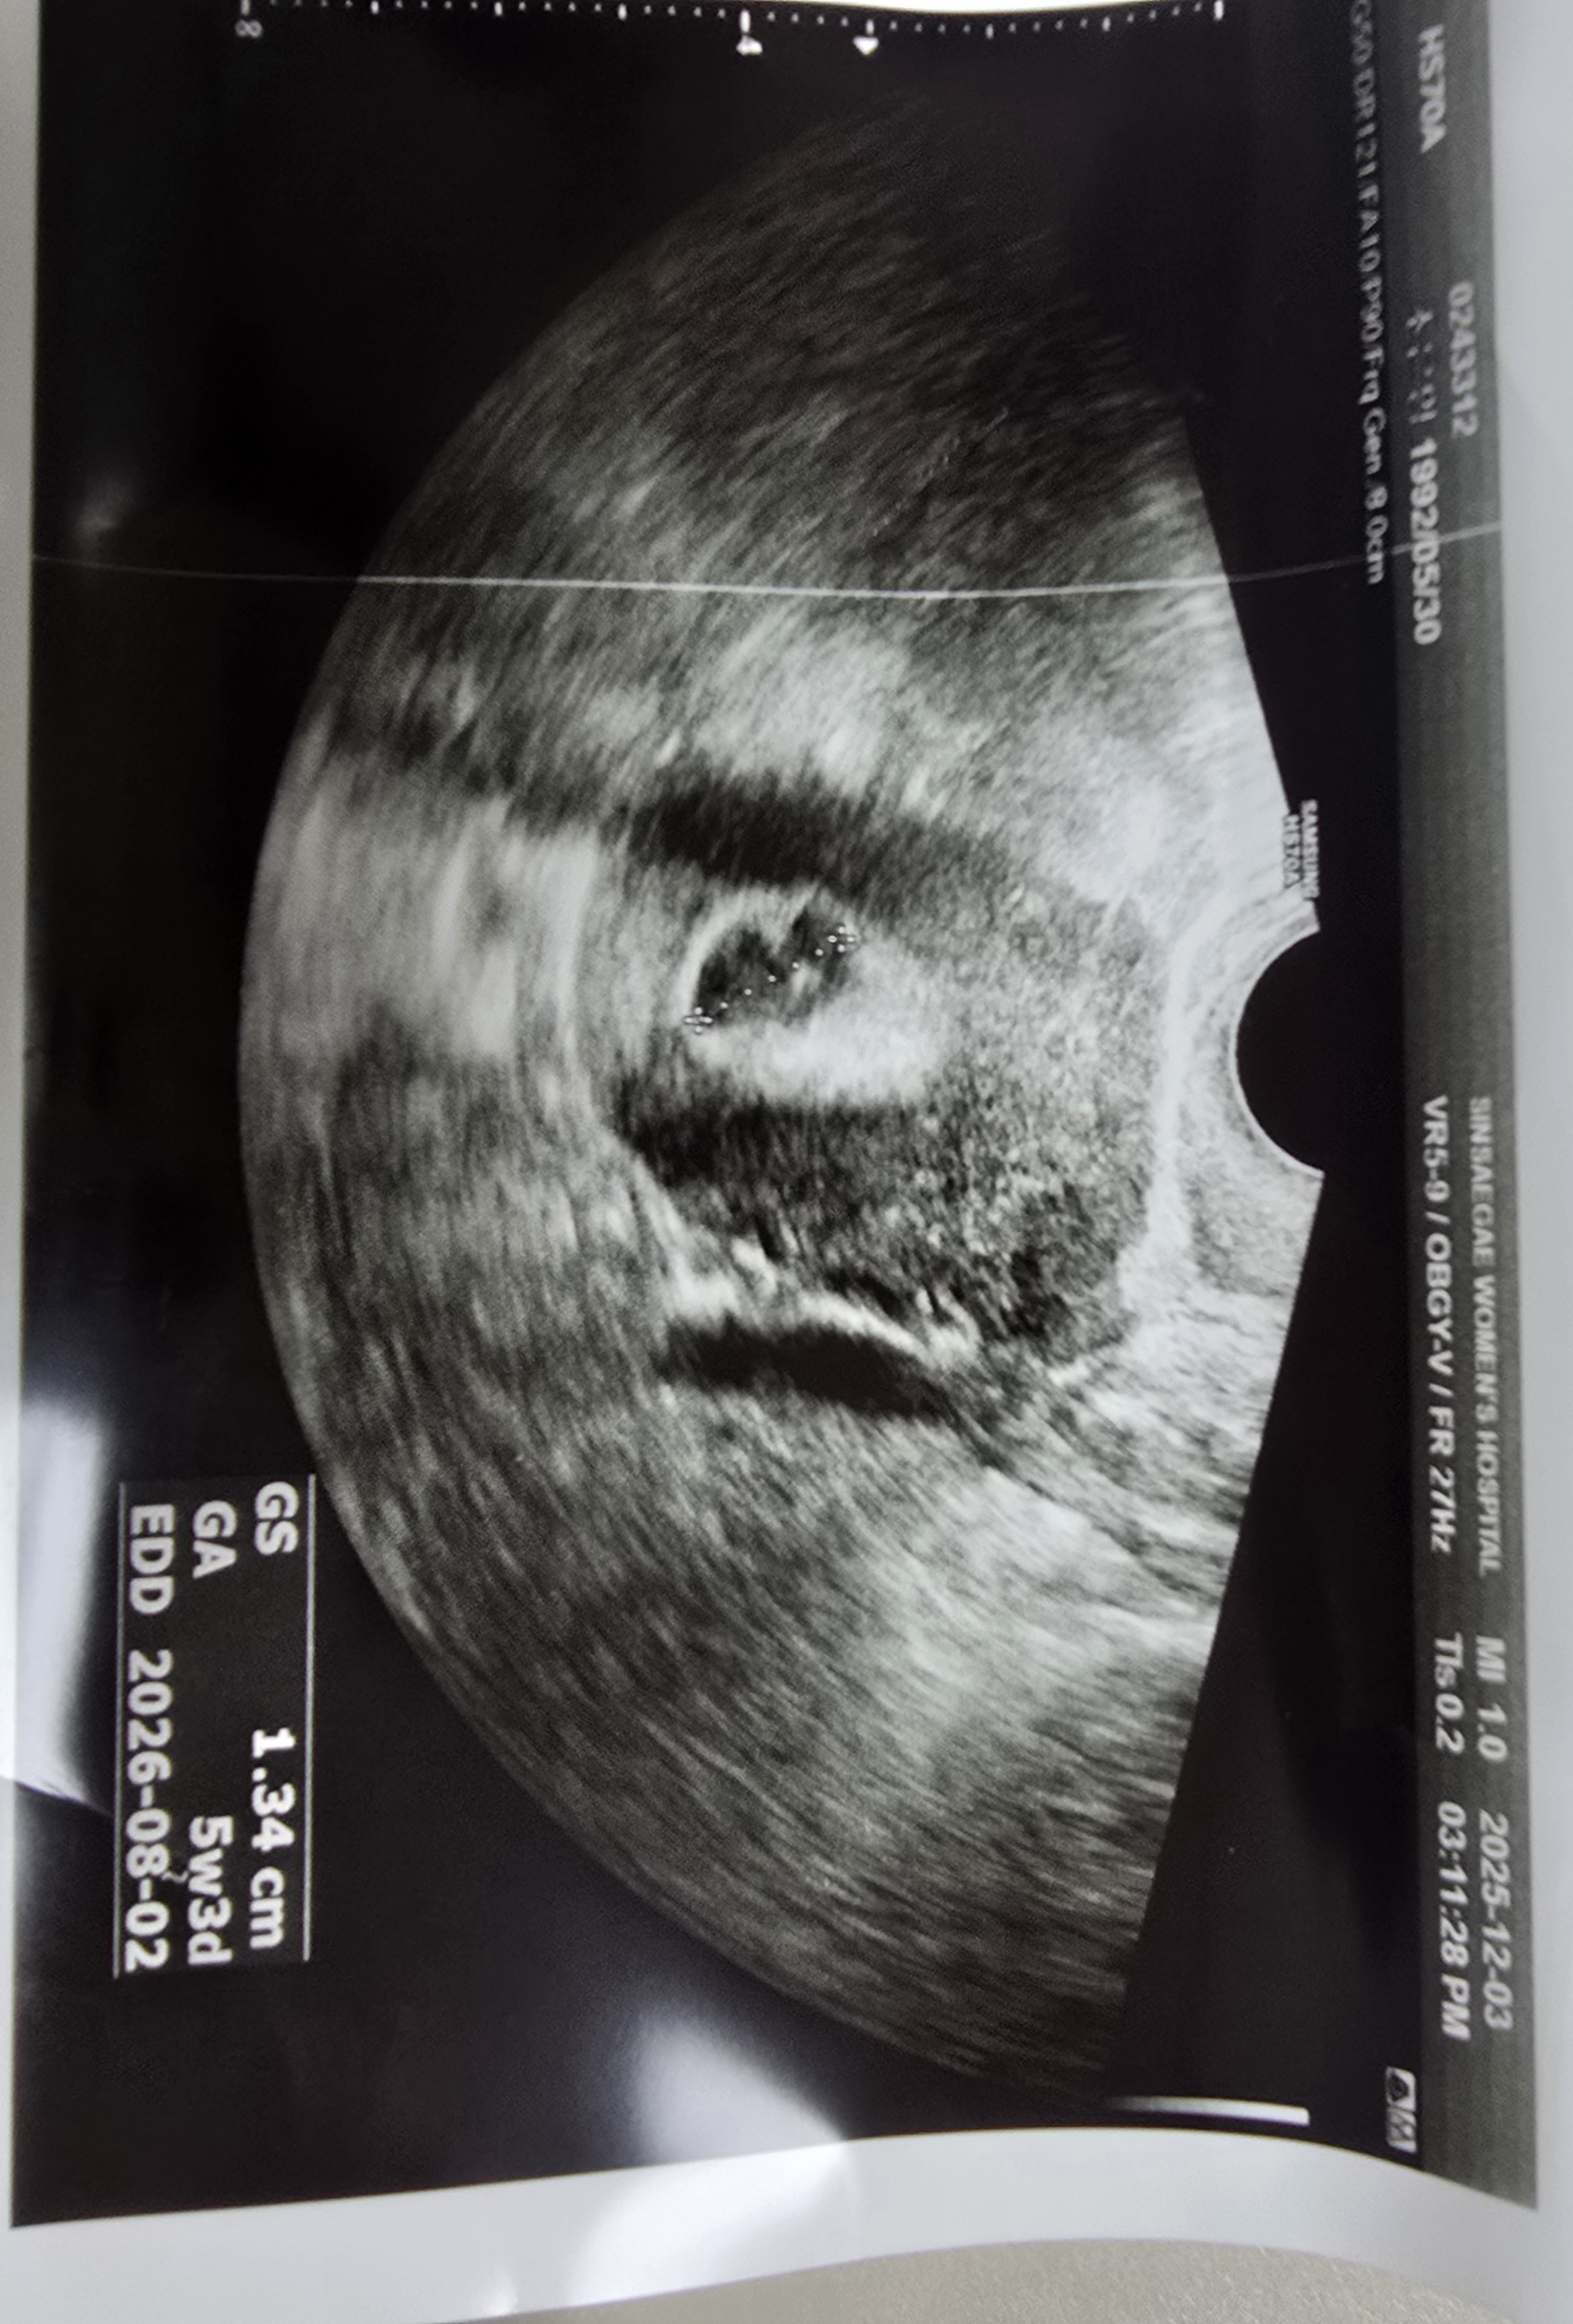

아기집모양이 찌그러져있어요

피고임도 많았고 출혈도 심했어요. 덩어리도 보이고요. 출혈이 일주일쯤 됐는데 피가 좀 갈색혈로 변하고 양도 많이 줄었어요. 그런데 배통증도 같이 사라져 유산된건가 해서 병원 다녀왔습니다. 원래 다니던 병원 아닌 처음간 병원 의사쌤이여서 그런지 아기집이라고 100프로 확신은 못한다 하셨어요.ㅠㅠㅠㅠ 아기집 맞고, 난황도 보이는거 같은데 어떻게 보이시나요? 찌그러져 있는것도 좀 위험하고 다음주 심장소리 들리는지 봐야된대요.